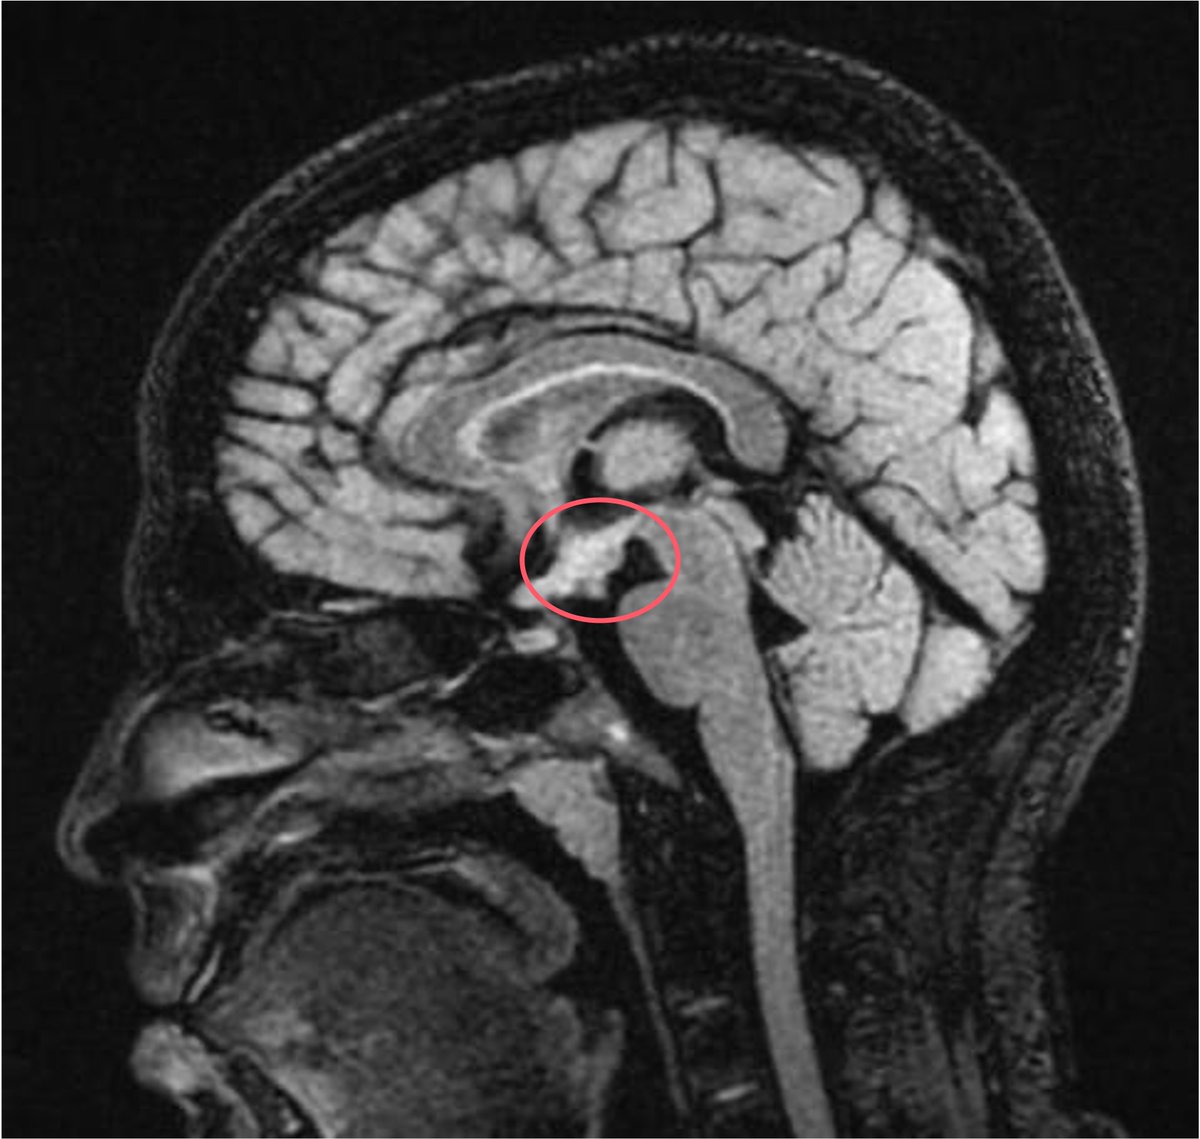

21 y/M 2018 - headache, LOW, low grade fever.Imaging had seller mass lesion for which referred to higher centre (didn't follow up). 2020 - Additiona